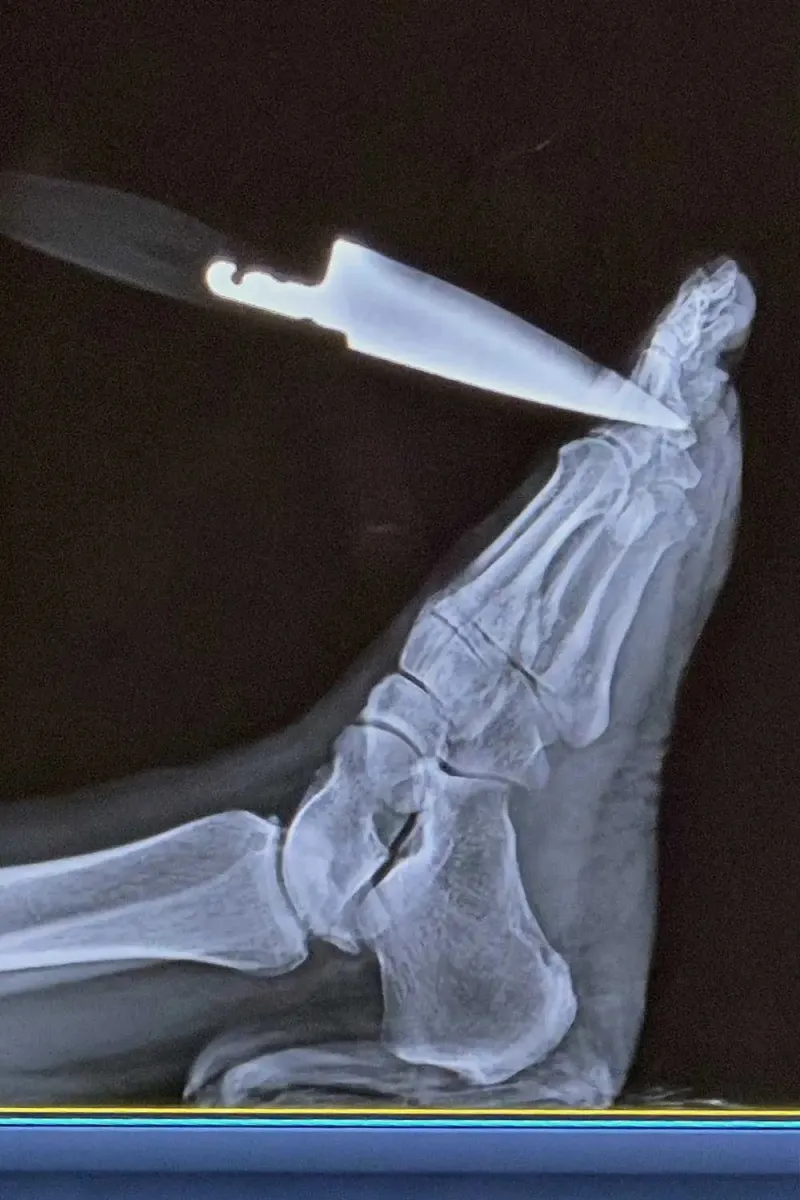

Марісса та ніж у нозі. Фото: Kennedy News

Ніж у нозі Марісси. Фото: Kennedy News